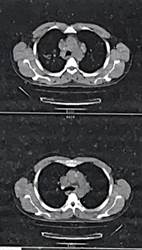

En la tabla 2 se pueden analizar los estudios paraclínicos realizados en agosto de 2023. En los estudios de imagen, la radiografía de tórax posteroanterior de agosto de 2023 (imagen 1) mostró opacidades bilaterales de predominio apical, tipo 2 de la Clasificación Internacional de la OIT. La tomografía computarizada (TC) toracoabdominal del mismo mes (imagen 2) evidenció opacidades bilaterales formando masas, principalmente en pulmón derecho, sin cavitaciones, desplazamiento bronquial por efecto de masa, nódulos subpleurales, alteración de arquitectura pulmonar; y una TC posterior realizada en clínica privada reportó imágenes hiperdensas en lóbulos superiores, probable cavitación ocupada en lóbulo superior derecho, fibrosis y patrón reticular grueso sin derrame pleural. Como parte del protocolo de estudio, se le realizaron las pruebas de función pulmonar donde se reportaron en febrero de 2024 una CVF (capacidad vital forzada) y VEF₁ (volumen de aire exhalado durante el primer segundo de la maniobra espiratoria forzada) al 60%, y en marzo de 2024 CVF 42% y VEF₁ 45%, confirmando deterioro funcional severo (imagen 3).

Imagen 1

Radiografía de tórax

![]() |

Nota: Radiografía posteroanterior de tórax donde se observan opacidades bilaterales de predominio apical, tipo 2 de la Clasificación Internacional de la OIT